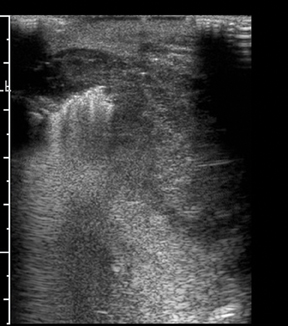

Her doctor recommended a thyroid ultrasound, a simple yet powerful diagnostic tool capable of revealing underlying thyroid issues. This is where a specialized ultrasound service for thyroid, scrotal, and breast health came into the picture, offering her a lifeline.

For Meera, the journey to understanding her health began with a simple appointment. The skilled technicians and state-of-the-art equipment ensured she received precise results. The thyroid ultrasound revealed an underactive thyroid, a condition that, once identified, could be effectively managed with medication and lifestyle changes.

This story is not unique to Meera. Across India, countless individuals face similar health mysteries. For instance, consider Rajesh, a 40-year-old teacher from Delhi, who noticed a small lump in his scrotum. The fear of the unknown gripped him, as cancer was a word he couldn't ignore. With the help of a scrotal ultrasound, Rajesh was able to discern that the lump was benign, a huge relief that allowed him to continue his life without the weight of worry.

Similarly, breast health is a pressing concern for many women. Anjali, a 28-year-old software engineer in Bangalore, discovered a lump in her breast during a routine self-examination. The fear of breast cancer loomed large, but a quick ultrasound provided a clear picture, showing it was a non-cancerous cyst. This information not only eased her fears but also underscored the importance of regular check-ups.